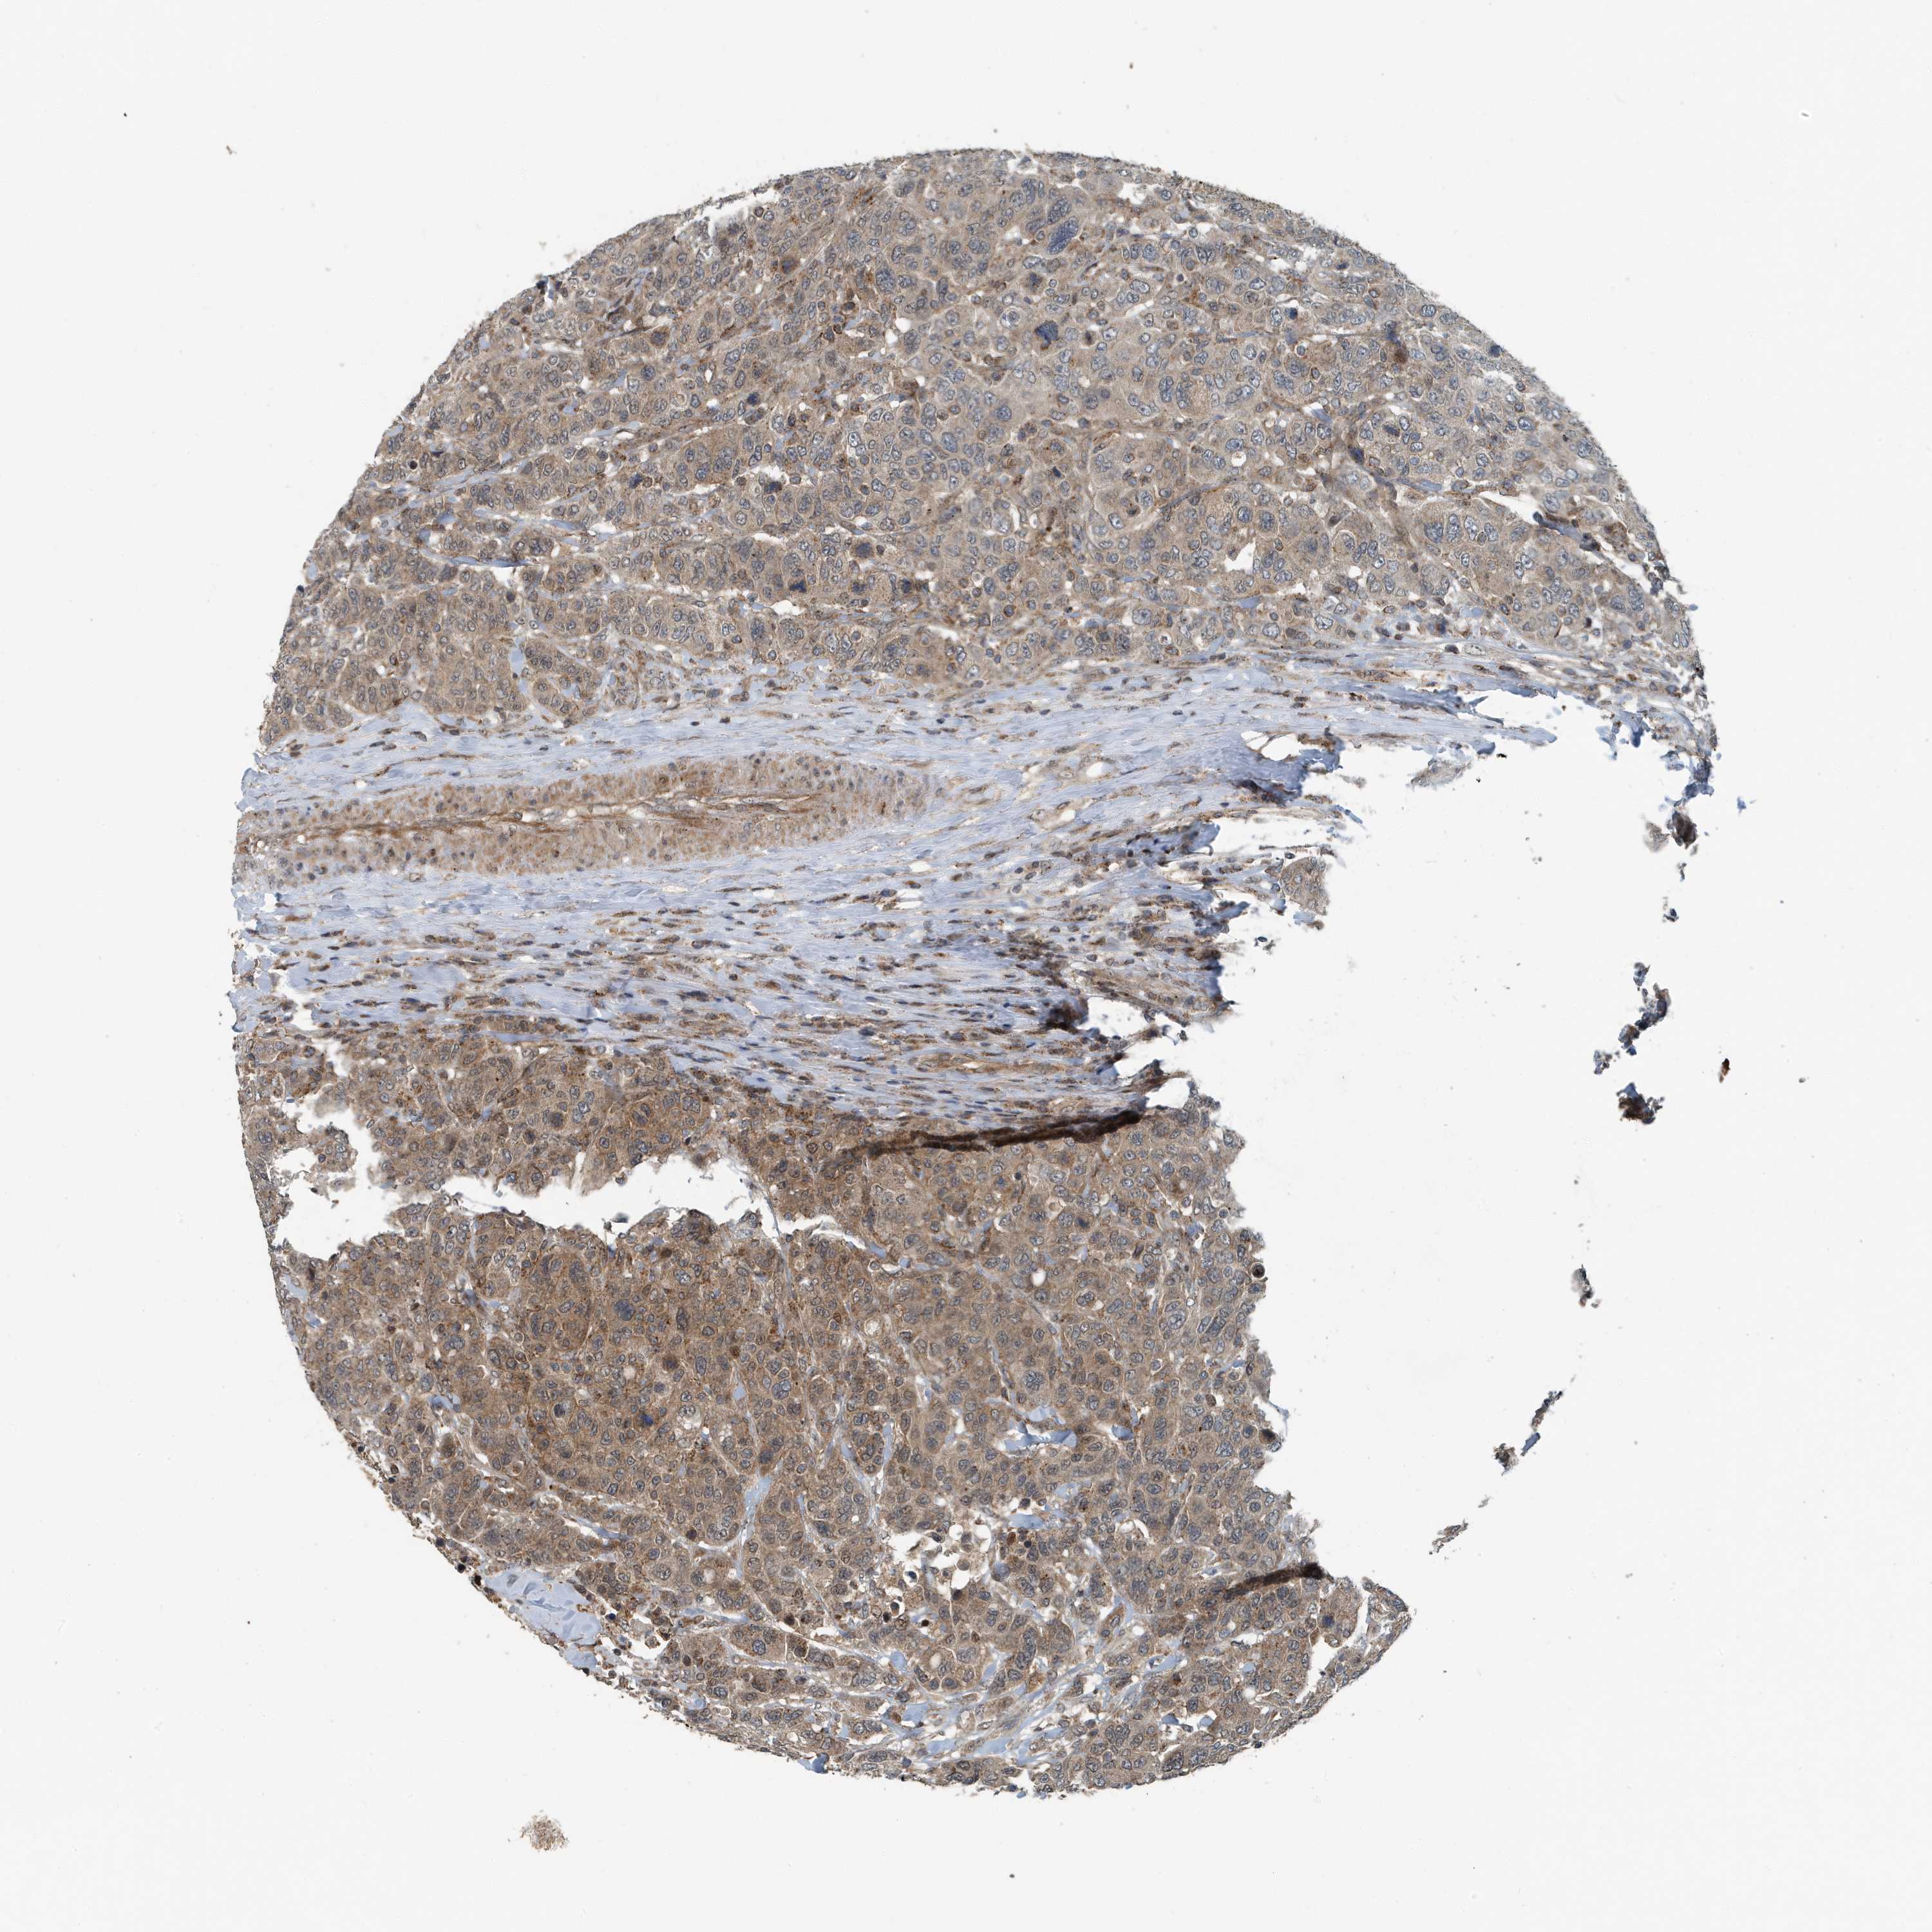

BRCA TCGA BRCA VALIDATION PROTEIN EXPRESSION